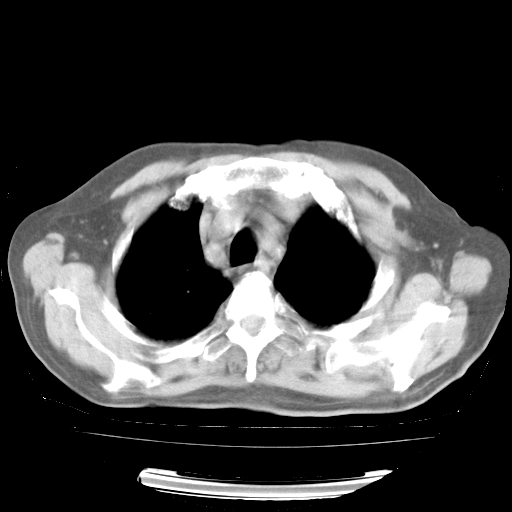

4月28日肺部CT